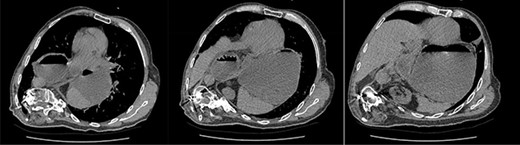

A 67-year-old man presented to the emergency department with sudden onset epigastric abdominal pain and vomiting, on a background of a known hiatus hernia awaiting surgical management. The patient continued passing flatus but was not able to tolerate any per oral fluid intake, vomiting any intake that was attempted. Medical history was relevant for severe KS, spina bifida, reflux, recurrent urinary tract infection, and an anterior approach spinal fusion surgery. Examination was significant for severe KS, with a soft and non-tender abdominal examination. Biochemically, the patient had a very mildly raised white cell count of 12.6 † 109/l. A CT of the abdomen and pelvis was obtained that identified the progression of a known hiatus hernia in comparison with an earlier CT, containing the distal portion of the stomach. The CT showed a distended and fluid filled oesophagus and stomach, along with fat stranding around the distal stomach, concerning for obstruction and possible strangulation of the moderate hiatus hernia, along with the known severe KS (see Figs 1 and 2). A nasogastric tube was placed to decompress the stomach (see Fig. 3). Following discussion with the patient regarding their current presentation and risks of operative management, laparoscopic hiatus hernia repair and fundoplication was undertaken, which was uncomplicated, although the dissection was difficult secondary to the severe scoliosis. Intra-operatively, it was noted that the hernial sac contained a grossly dilated stomach, with all hernial contents assessed as being viable, with nil signs of ischaemia. The peritoneal sac was not resected and left in situ, with a four-stitch horizontal posterior cruroplasty undertaken, along with a 180-degree anterior fundoplication. There was concern that recovery may be complicated by respiratory failure due to the severe KS; however, the patient had no respiratory compromise, begun passing flatus, opened his bowels, and tolerated a puree diet in the days following the operation. At post-operative clinic review 4 months following the hiatus hernia repair, the patient was well, described nil issues, and was tolerating a full diet.

Axial slices of CT scan showing a moderate hiatus hernia with concern for obstruction and strangulation, with severe kyphoscoliosis.